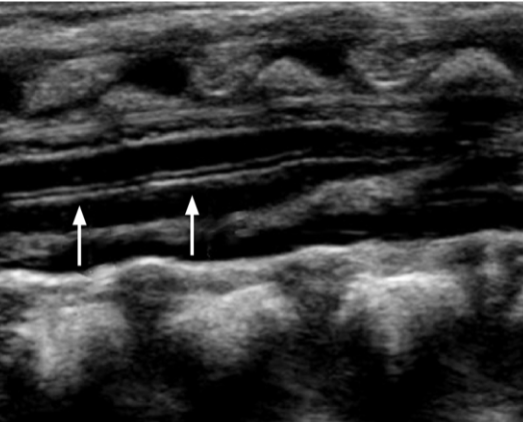

Which mode of ultrasound may be used to document the synchronized oscillations of the cauda equina and spinal cord?

M-mode